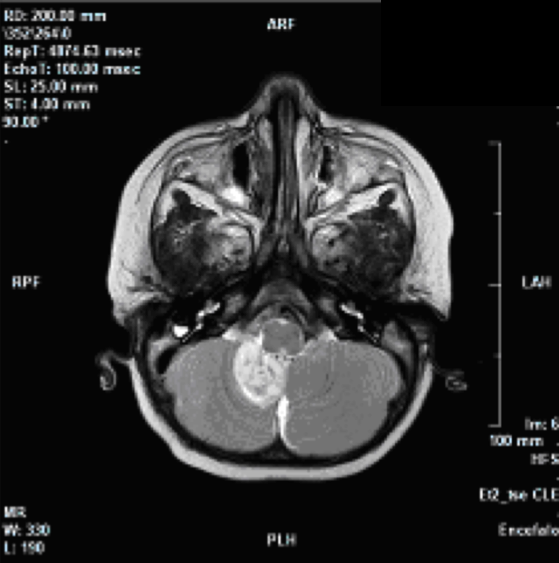

Il piccolo A. di 7 mesi, � giunto in PS verso le 21.30 di sabato sera, appena dopo essere sbarcato con la famiglia dal traghetto che doveva portarli in vacanza. Durante la traversata in occasione di un cambio pannolino A. � caduto dal letto a castello, sbattendo la fronte. Per questo i genitori preoccupati lo portano nel nostro ambulatorio di accettazione pediatrica. All'E.O.G. il piccolo � apparso in discrete condizioni generali, vigile, reattivo; pupille isocoriche, isocicliche e normoreagenti alla fotostimolazione; obiettivit� cardiopolmonare nella norma, FC 100 bpm, PA 90/60 mmHg, Sat.O2 100% in aria ambiente; addome trattabile, apparentemente n� dolente n� dolorabile; lieve escoriazione in regione frontale sx. Sottoposto a visita neurochirurgica (nella norma), � stata predisposta l'osservazione presso la Clinica Pediatrica. All'ingresso in reparto, ha eseguito esami ematochimici di routine e profilo coagulativo risultati nella norma. Verso le 22.30 in seguito alla comparsa di due episodi di vomito il piccolo ha iniziato terapia reidratante con souzione bilanciata alla velocit� di 30 ml/h. Dopo una notte tranquilla, per il riscontro di sonnolenza ed un ulteriore episodio di vomito � stata richiesta TAC-cranio urgente che ha escluso lesioni post-traumatiche, evidenziando per� un'area ipodensa in fossa cranica posteriore, a livello della tonsilla di dx, di dubbia interpretazione. Per tale motivo il giorno seguente, il paziente ha eseguito RMN-encefalo con MDC e Angio-RMN encefalo. Il primo esame ha confermato in sede cerebellare inferiore dx la presenza di una lesione espansiva di circa 1,5 x 1,5 x 2,5 cm, disomogeneamente iperintensa in T2, isoiperintensa in Flair, ipointensa in T1 con restrizione della diffusione ed esili strie di enhancement dopo la somministrazione di MDC. (Figura 1 e Figura 2)

Nel suo contesto si apprezzano minute aree ipointense in T2 da riferire a esiti di micro sanguinamenti. La lesione anteriormente contrae rapporto con l'arteria cerebellare postero inferiore, esercitando una lieve impronta sulla superficie posterolaterale dx del bulbo e infiltrando la tonsilla cerebellare omolaterale che appare modicamente ptosica al di sotto del forame occipitale (5 mm); superomedialmente esercita una modica impronta sul verme. Un'alterazione di segnale che potrebbe rappresentare segno d'infiltrazione controlaterale si apprezza a livello della tonsilla cerebellare di sx. Lateralmente la lesione appare delimitata da una stria di alterato segnale compatibile con edema perilesionale. Le restanti strutture cerebrali risultano nella norma. Lo studio angioRMN non evidenzia presenza di definite alterazioni a carico dei principali vasi arteriosi intracranici. Per le caratteristiche evidenziate, la giovane et� e la sede, il radiologo pone in prima ipotesi il sospetto di medulloblastoma, non potendo escludere per� una forma desmoplastica o un ependimoma. Non si rilevano ulteriori alterazioni di segnale a carico delle regioni sotto e sopratentoriali. Data la lontananza dal domicilio, i genitori del piccolo, in accordo coi sanitari, decidono di trasferire A. presso l'Unit� di Neurochirurgia della loro citt�. All'arrivo in Ospedale il piccolo appare sveglio, reattivo, con pupille isocoriche, normoreagenti. Muove i 4 arti senza apparenti asimmetrie, n� clonie. Presenta buon tono di arti, tronco e capo. Il piccolo A. � sottoposto ad intervento chirurgico per asportazione della lesione. Dall'esame istologico si evidenzia che il materiale accoglie lembi di parenchima cerebellare con associate numerose strutture vascolari proliferanti (saltuarie figure mitotiche) per lo pi� a parete sottile sullo sfondo di aree di microinfarcimento emorragico, numerosi elementi istiocitari e fenomeni di densa gliosi perilesionale. Particolarmente in due frammenti si repertano inoltre espressioni di necrosi e di flogosi suppurativa. I reperti suggeriscono una natura primitivamente vascolare della lesione di tipo angiomatoso.

Figura 2. RM dell'encefalo